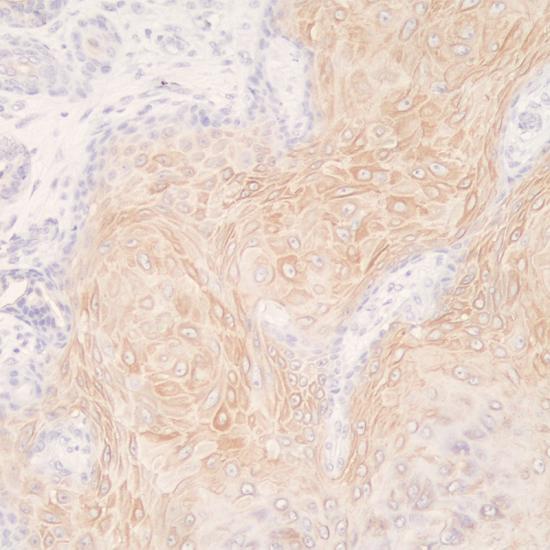

鼠抗人細胞角蛋白16(CK16)單克隆抗體

CK16在包括皮膚的許多復(fù)合上皮組織中組成型表達,在創(chuàng)傷愈合、牛皮癬和癌癥(鱗狀細胞癌)等有利于加強增殖或異常分化的條件下被誘導(dǎo)表達。CK16主要標記角化和增生的鱗狀上皮,主要用于鱗狀細胞癌的診斷。